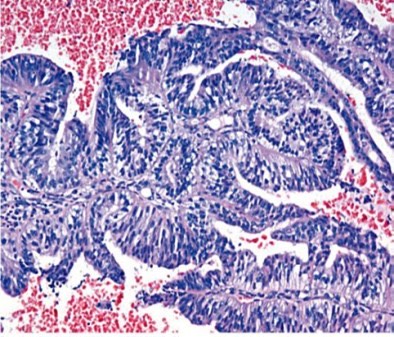

1973. На изображении представлен гистологический тип опухоли, а именно